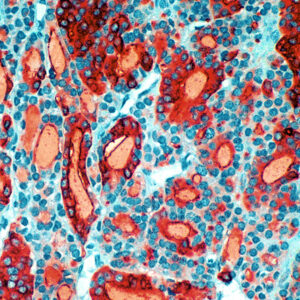

Anti-Cytokeratin 14

Keratins are intermediate filament proteins expressed by epithelial cells in cytoplasm. Mitotically active basal layers of most stratified squamous epithelia cells express 10% to 30% of their total protein as keratin. Cytokeratin 14 (CK14) is a 50-kDa keratin expressed in abundance in epidermal cells, basal cells, mesothelial cells, stratified epithelial cells, and myoepithelial cells in various tissues including prostate and breast. CK14 is helpful in the identification of breast cancer with basal phenotype